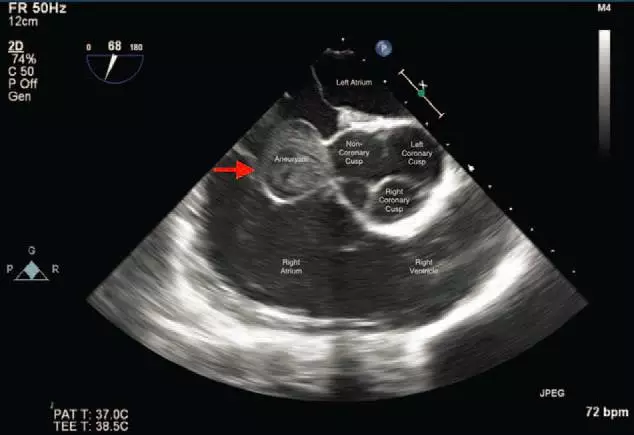

圖示患者心臟超聲檢查結(jié)果

術(shù)中行經(jīng)食管超聲心動圖以進一步評估腫瘤情況,結(jié)果發(fā)現(xiàn),主動脈瓣非冠狀尖呈明顯外翻,邊緣清晰,伴主動脈根增厚(真性動脈瘤),彩色多普勒超聲進一步發(fā)現(xiàn)未破裂的瓦氏竇動脈瘤,在心臟舒張期呈自發(fā)性回聲漩渦。

基于上述檢查結(jié)果,外科醫(yī)生商議立即中央靜脈置管,開展體外循環(huán),行主動脈切開術(shù),采用心包補片修補瓦氏竇動脈瘤。

臨床上 MRI 可用于做出初步診斷,但經(jīng)食管超聲心動圖診斷的敏感性和特異性較高,可有效鑒別動脈瘤或血栓。